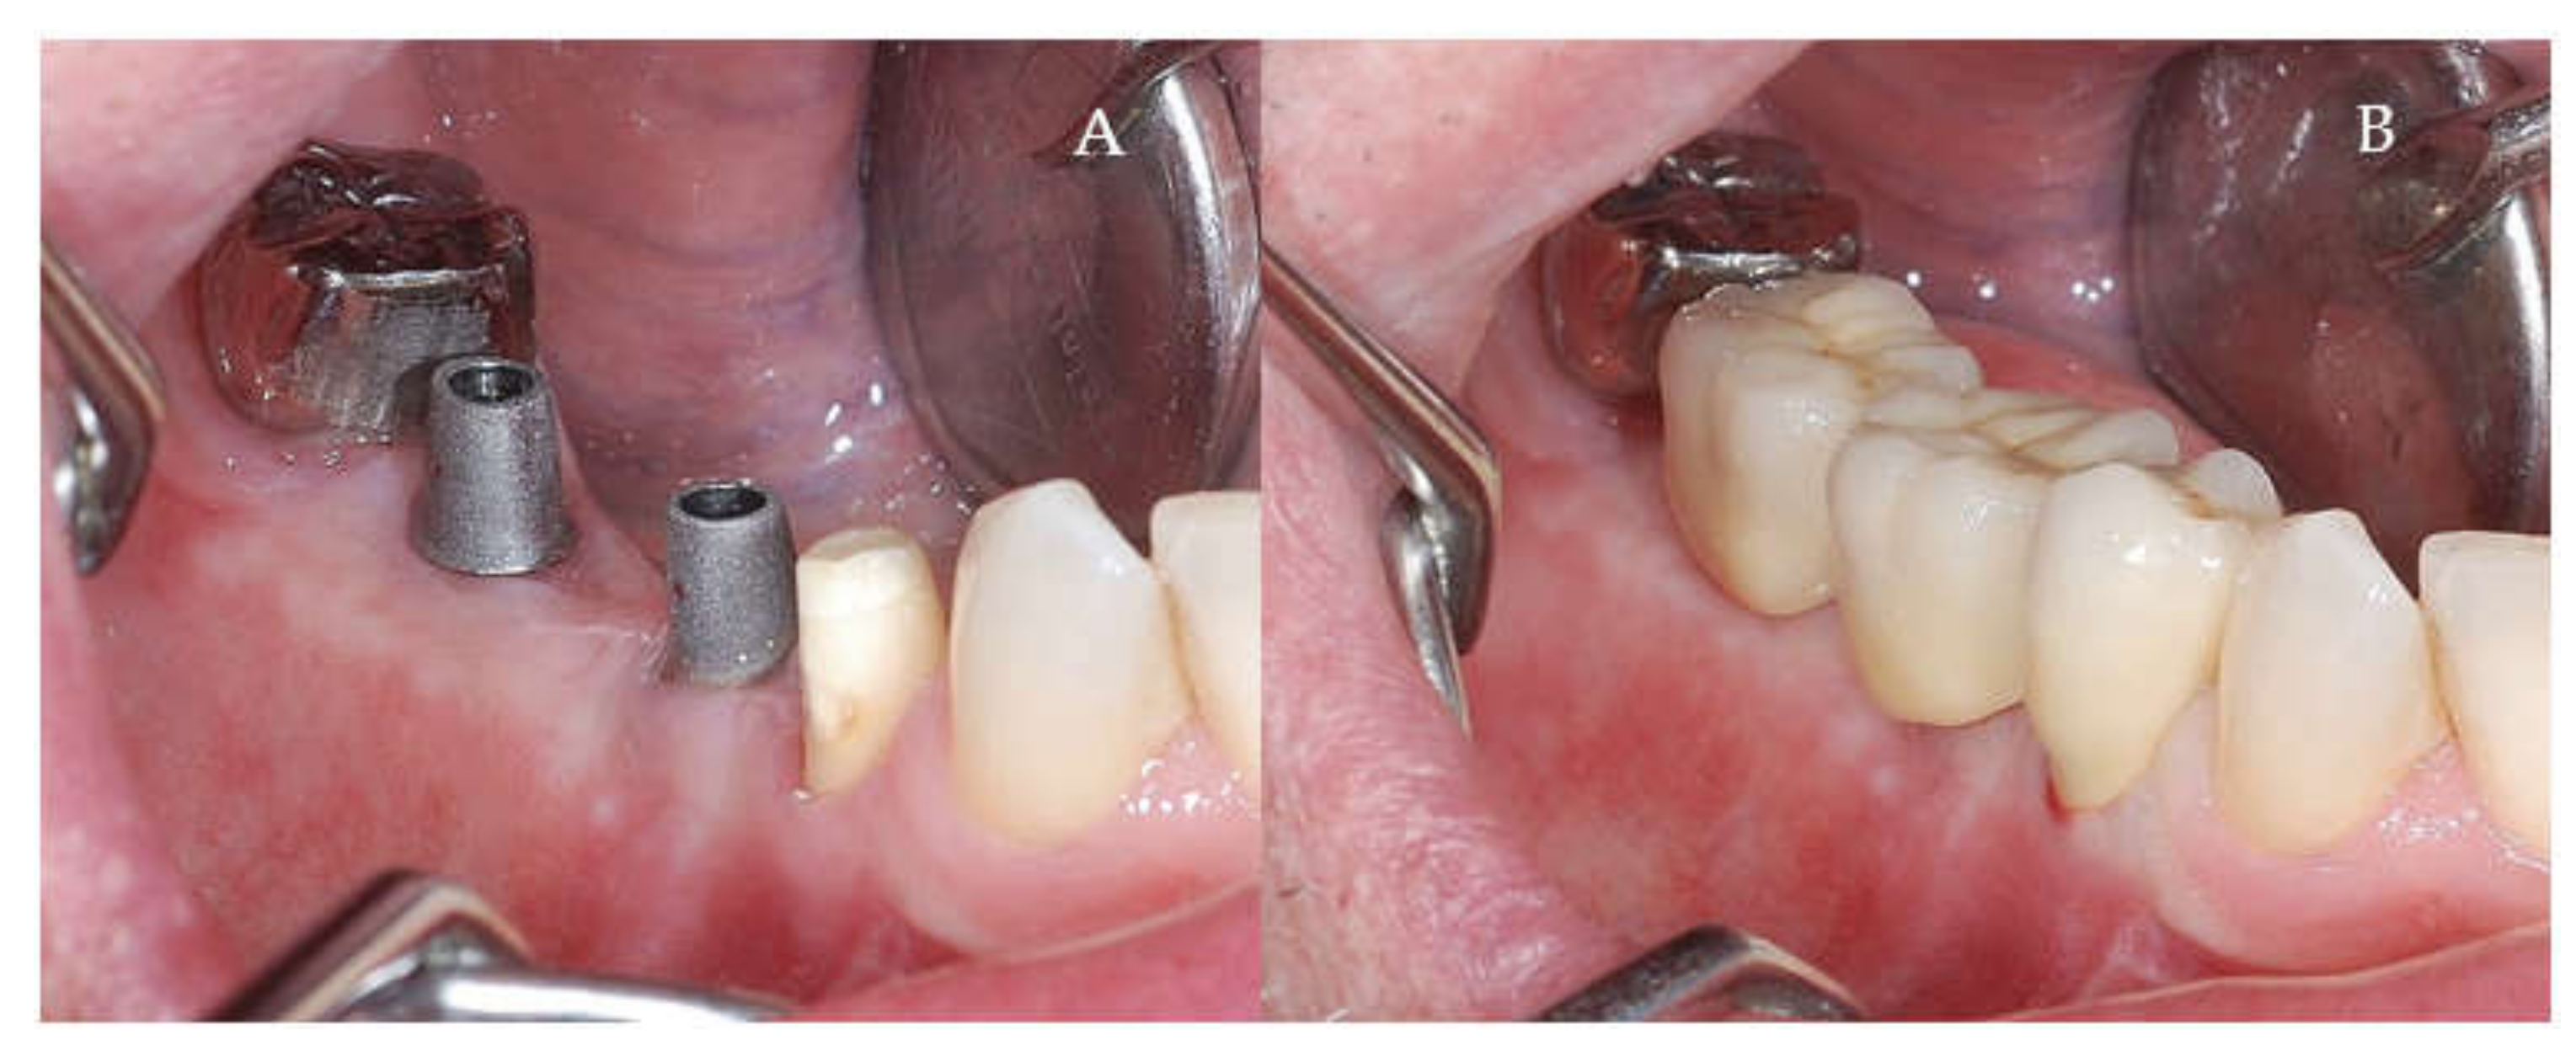

Clinical and CBCT aspects of patient from the test group, describing the stages of S-GBR technique and implant-prosthetic stage, are presented in Figure 1, Figure 2, Figure 3, Figure 4, Figure 5, Figure 6, Figure 7, Figure 8, Figure 9, Figure 10 and Figure 11. CBCT exam allows the evaluation of the horizontal alveolar bone defect and the position of the mandibular alveolar nerf (Figure 1A,B). Figure 1C,D show cross-sectional CBCT aspects of the implant sites. Figure 2 shows the narrowed mandibular alveolar bone with horizontal resorption. Figure 3 shows the exposed buccal surface of the alveolar ridge with severe horizontal resorption, after flap opening. The inserted implants (4.5 mm diameter, 11.5 mm length) and osteosynthesis screws (45° from the occlusal plan) are shown in Figure 4A. The placement of graft (autologous bone and xenograft) and collagen membrane is shown in Figure 4B. Figure 5A shows tension-free sutures, due to periosteal incisions alveolar ridge. Figure 5B shows clinical aspect at 7 months after surgery, with gingival tissue adherent on the reconstructed alveolar ridge. Figure 6 shows OPG aspect at follow-up of 7 months, with osseointegration of the dental implants. Figure 7A shows clinical aspect before osteosynthesis screws removal. Figure 7B shows clinical aspect after osteosynthesis screws removal. Figure 8A shows healthy peri-implant soft tissues. Figure 8B shows repositioning key for perfect position of abutments. Figure 10A,B show clinical aspects of implant-supported prosthetic restoration. Figure 11A,B show CBCT aspects of Osseo integrated dental implants at 24 months follow-up.

Figure 10.

(A,B) Final prosthetic stage. (A) Titanium Abutment (B) Cemented metal-ceramic crowns.